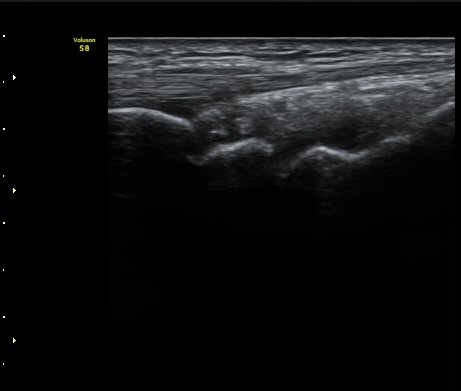

ÃÊÀ½ÆÄ °Ë»ç

¼Õ¸ñÀÇ Á¾´Ü

ÁÖ»ó°ñ ¼±»ó°ñÀýÀº ´Ü¼ø¹æ»ç¼± ÃÔ¿µ ½Ã È®ÀεÇÁö ¾ÊÀº °æ¿ì°¡ ¸¹Àºµ¥ ÀÌ ¶§ ÃÊÀ½ÆÄ

°Ë»ç°¡ ÁÖ»ó°ñ °ñÀý Áø´Ü¿¡ ¸Å¿ì À¯¿ëÇÏ´Ù. ±×·¯¹Ç·Î ¼Õ¸ñ ´ÙÄ£ ÈÄ Áö¼ÓÀûÀÎ ÅëÁõÀ»

È£¼ÒÇϰí ÁÖ»ó°ñ ºÎÀ§ ¾ÐÅëÀ» º¸ÀÌ´Â °æ¿ì ÃÊÀ½ÆÄ°Ë»ç¸¦ ½ÃÇàÇÏ¿© ÁÖ»ó°ñ °ñÀý ¿©ºÎ¸¦

È®ÀÎÇØ¾ß ÇÑ´Ù.

ÃÊÀ½ÆÄ°Ë»ç¸¦ ½ÃÇàÇÒ ¼ö ¾ø´Â °æ¿ì´Â ÄÄÇ»ÅÍ ÃÔ¿µ°Ë»ç¸¦ ÁÖ»ó°ñ °ñÀýÀ» È®ÁøÇÒ ¼ö ÀÖ´Ù.